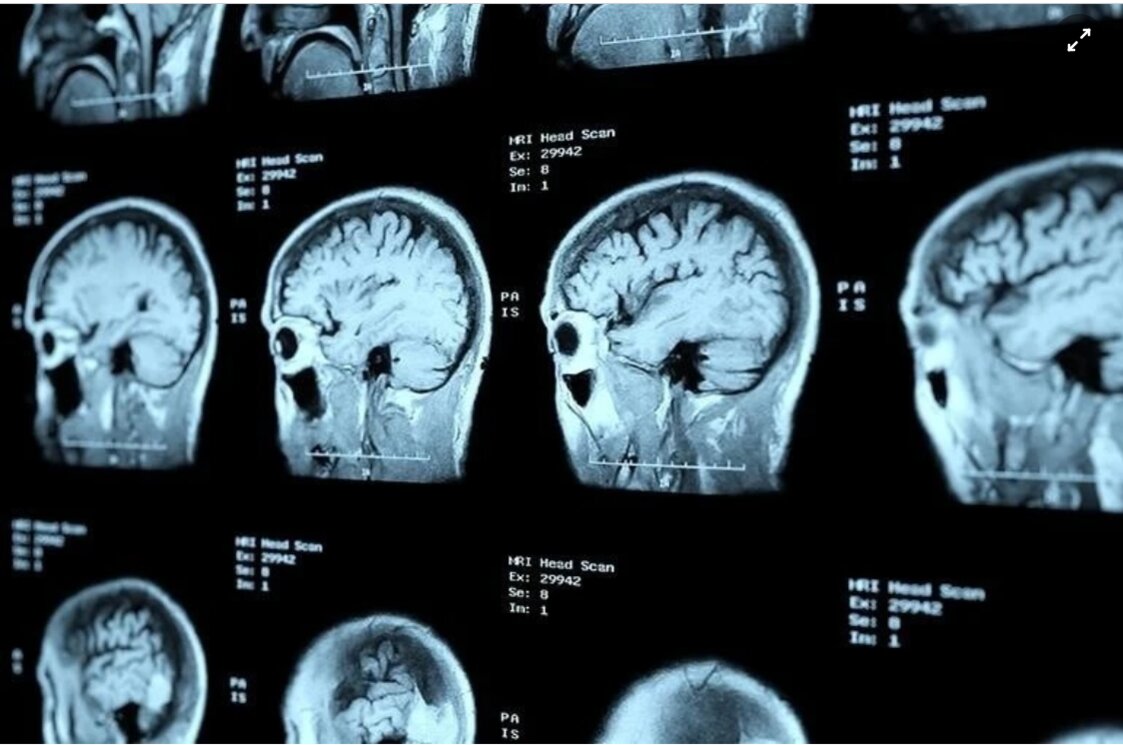

Ở khoa Cấp cứu, các bác sĩ nhanh chóng đánh giá tình trạng. Những dấu hiệu chóng mặt dữ dội, thất điều nửa người phải cùng huyết áp tăng vọt tới 200/100 mmHg khiến họ nghĩ ngay đến đột quỵ. Bệnh nhân được đưa đi chụp MRI ngay trong đêm. Ê-kíp cấp cứu lập tức dùng thuốc tiêu sợi huyết.

Đột quỵ là một trong những nguyên nhân tử vong hàng đầu tại Việt Nam. Ảnh: Shutterstock.